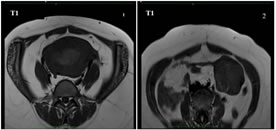

A 40 years old nulliparous premenopausal woman, presented to the gynaecology OPD with a chief complaint of abnormal uterine bleeding and pain in the lower abdomen, predominantly towards left side since an year. The patient had no significant relevant past history or risk factors. The clinical examination of the abdomen revealed no palpable mass. Abdominal ultrasound revealed a solid heterogeneously hypoechoic mass lesion arising from the left ovary, measuring approximately 55x53x50mm and showing moderate colour flow on colour doppler. A moderately enlarged uterus with increase in endometrial thickness was also identified (24 mm). No suspicious abdominal lymphadenopathy was noted. MRI Pelvis showed a single large well defined moderately enhancing, mixed predominantly solid lesion measuring approximately 60x58x53mm (MLXCCXAP) in the left adnexa, which is heterogeneously hypointense on T1W, Isointense with central hypointense areas on T2W, heterogeneously hyperintense with central hypointense areas on T2W/STIR and showing no restricted diffusion on DWI. Uterus appears moderately enlarged with multilobulated heterogenous diffuse moderately enhancing solid areas and non-enhancing cystic areas within the endometrial cavity. No suspicious pelvic lymphadenopathy was noted. Serum CA-125 concentration was elevated,95 U/mL (normal range <35 U/mL). After the positive frozen section pathological examination of the left ovary, the patient underwent a total abdominal hysterectomy, bilateral salpingo-oophorectomy, bilateral pelvic and para-aortic lymphadenectomy, and omentectomy. Pathological findings revealed a well-differentiated endometrioid carcinoma of the left ovary and a well-differentiated endometrioid carcinoma of the endometrium. The patient did not receive any adjuvant chemotherapy or radiotherapy and was suggested for a regular follow-up. Up to the last follow-up visit (April 2021), the patient had no recurrence.

Figure 3                                                          Figure 4

Figure 1: Mixed predominantly solid, heterogeneously hypoechoic mass lesion in the left adnexa; Figure 2: Mass lesion showing moderate vascularity on application of colour Doppler; Figure 3: Increased endometrial thickness with multilobulated heterogenous diffuse solid areas and cystic areas; Figure 4: Few solid components showing mild vascularity on application of colour Doppler;